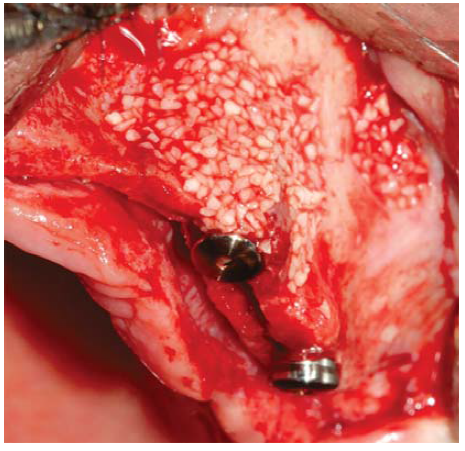

A full thickness incision over the crest was performed, raising a mucoperiosteal flap exposing bone table up to 4 mm from the top of the crest in vestibular direction; from that point the flap was divided into partial thickness (Figure 3). After this, impact points were marked in designated places according to surgical guide for implant placement; perforations were initiated with a 1.6 mm diameter burr in order to determine desired implant depth and axis. After this, a ridge was created on the crest with a diamond burr, fracturing cortical bone to create chisel's access to cancellous bone, and with the aforementioned, bone tables were separated until reaching a 5 mm depth (Figures 4 y 5). Perforations were further continued with a 2.0 diameter burr (Figure 6), and vestibular table expansion was undertaken creating greenstick fracture with the expanders, until reaching sufficient osseous bed diameter (3.2 mm diameter) (Figures 7 y 8). Implants were then placed at a 25 rpm speed and 35 Nem torque (Figures 9 y 10). After this, a particulate bovine bone graft was placed (Bonefill® Bionnovation Biomedical, Sao Paulo, Brazil) with the aim of preserving integrity of vestibular bone tables (Figure 11). All these procedures were repeated for placement of all six implants. Finally, sutures were undertaken with monofilament nylon 5/0.

For this surgical procedure, the patient received the same pre-surgical preparation than that used for the upper jaw. Procedure was initiated with an incision between grooves at the level of all teeth, after which a mucoperiosteal flap was raised. Teeth were then extracted and adjacent granulation tissue was removed, trying to preserve all bone remnants. After this, bone ridge was regularized and remodeled using multi-laminated burrs with abundant irrigation. With a conventional burr sequence, perforations were then initiated at places designed for implant placement. After this, all four implants were placed, locating prosthetic platforms at one same level. Since there was presence of bone defects and three walls around the implants, particulate bovine bone graft was placed (Bonefill® (R) Bionnovation Biomedical, Sao Paulo, Brazil). Finally, sutures were applied with monofilament nylon 5/0.

The Split Crest technique provided horizontal ridge increase of about 1-4 mm; the upper jaw exhibited the greatest increase (4-3 mm) when compared to the lower jaw (1-1.5 mm).14 Likewise, greater numbers of complications have been reported when this technique has been used in the lower jaw.18 Therefore, indications for this procedure are more frequent and bear better prognosis when used in the upper jaw. It is worth mentioning there is controversy with respect to use of biomaterials during performance of Split Crest procedures. Use of membranes,14,19 bone grafts17 and materials such as tricalcium phosphate β (β-TCP) associated to platelet rich plasma13 have been described.

It has been reported that use of membranes as a barrier along with bone expansion entails greater difficulty for flap primary healing, increasing possibility of membrane exposition and infection during postoperative periods.20 Other reports compare intercortical bone space obtained after expansion with an extraction site that does not require filling with graft, they highlight the importance of periosteum and matrix in the regenerative process.21 Nevertheless, the present article describes use of bone graft composed of bovine inorganic matrix to fill osseous beds resulting from table division. Thus, the bone graft is surrounded by bone walls and also covered by periosteum, allowing ingress of osteoblasts and pre-osteoblasts into the graft.17,22 Bone reparation followed by this procedure is similar to that of a fracture, non-elevated vestibular mucoperiosteum is responsible for vascular nutrition and fixation of mobilized bone segment. After a five month period, a trabeculated area was observed with mature bone characteristics and remodeling capacity as well as the ability to withstand functional loads through the implants.23 For this reason reports advise to wait for a six month healing period before loading the implants.13,14,17